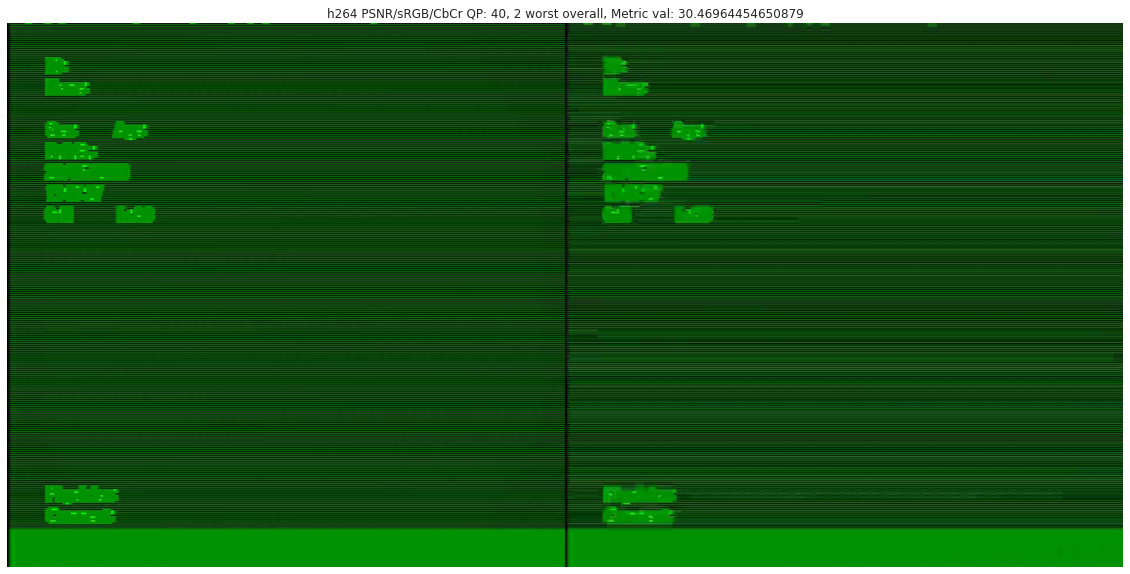

Compression quality: Figure 1 (middle) shows the compression rate versus frame quality distribution for H264 and HEVC. Importantly, we see that H264 and HEVC compress the most medically relvant frames statistically significantly worse: treating each QP value separately, a two-sided Kolmogorov-Smirnov test between distribution of PSNR-CbCr shows that the frame quality is lower for polyp frames than for all frames. For each QP value, , , H264 (HEVC) maximum p-value over all tests is (), mean test statistic (). For the same test with PSNR-Y, see the Appendix. Figure 2 top two rows show the lowest quality compressed frames inside the body according to PSNR-CbCr, with and without polyps (for the absolute worst quality compressed frames, see the Appendix).

A.3 Lowest quality compressed frames